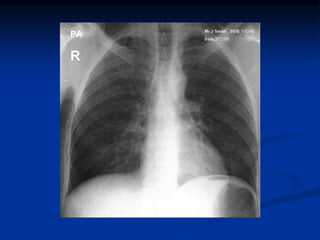

EXAME FÍSICO NORMAL

INSPEÇÃO

ESTÁTICA: TÓRAX DE FORMA NORMAL, SEM ALTERAÇÕES DE PARTES MOLES E

ÓSSEAS, SEM ABAULAMENTOS E RETRAÇÕES

DINÂMICA: FR = 16 MPM; RITMO REGULAR E SINCRÔNICO COM OS MOVIMENTOS

ABDOMINAIS. EXPANSIBILIDADE PRESERVADA E SIMÉTRICA. AUSÊNCIAS DE

RETRAÇÕES

PALPAÇÃO

SENSIBILIDADE CONSERVADA, AUSÊNCIA DE CONTRATURA OU ATROFIA

MUSCULARES, AUSÊNCIA DE ENFISEMA SUBCUTÃNEO E CALOS ÓSSEOS.

EXPANSIBILIDADE CONSERVADA E SIMÉTRICA. FTV NORMODISTRIBUIDO.

AUSÊNCIA DE FRÊMITOS BRÔNQUICOS E PLEURAL

PERCUSSÃO

SCP PRESENTE E SIMÉTRICO. SUBMACICEZ HEPÁTICA À PARTIR DO 5º EICD.

MOBILIDADE DOS LIMITES PULMONARES PRESERVADA

AULCULTA

MV PRESENTE, NORMODISTRIBUÍDO. AUSÊNCIA DE RUÍDOS ADVENTÍCIOS.

AUSCULTA DA VOZ NORMAL